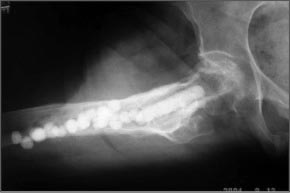

Здесь пример лечения антибиотическими бусами и форма для бус!

Имя     : Hip Infection 1.jpg

Тип     : image/jpeg

Размер  : 19350 байтов